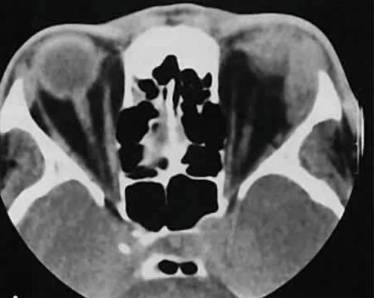

- компьютерная томография (например, шейного или поясничного отдела позвоночника);

- КТ.